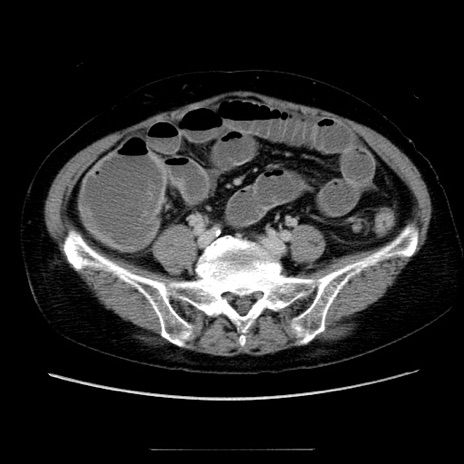

症例5(横断像)

【症例】70歳代女性

【主訴】お腹が張る

【現病歴】1週間くらい前から腹部膨満の自覚あり。昨日夜から増悪したため、本日救急外来受診。

【身体所見】意識清明、BT 36.5℃、BP 165/106mmHg、HR 80bpm、SpO2 98%、腹部:膨満、軟、自発痛・圧痛なし、触診にて不快感あり、腸蠕動音:減弱

【データ】WBC 12600、CRP 1.04